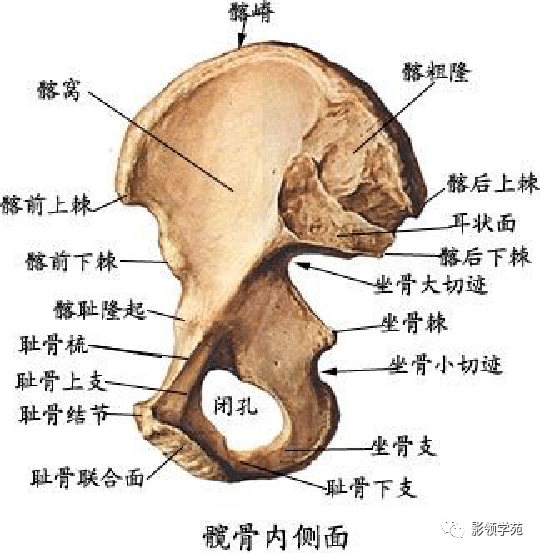

骨骼系统

骨骼系统